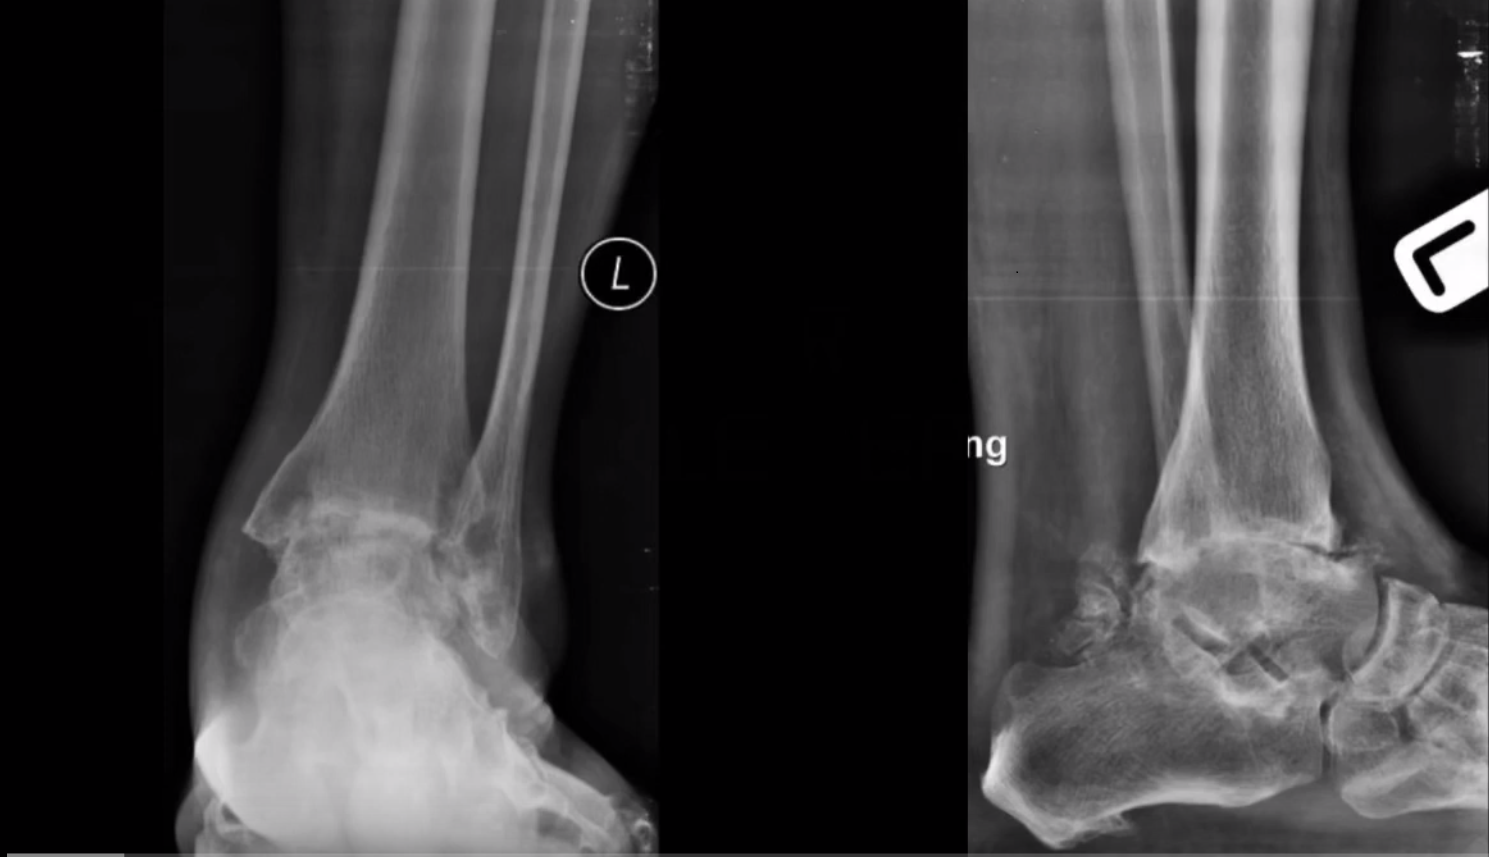

From footeducation.com

Ankle Arthritis FootEducation Septic Arthritis Foot X Ray Septic arthritis is an emergency that can lead to rapidly progressive, irreversible joint damage. Despite the urgency associated with this. Septic arthritis should be considered in adults presenting with acute monoarticular arthritis. Septic arthritis is seen on mri as joint effusion, typically with signs of inflammation including pericapsular edema and marginal bone marrow edema at the. Septic arthritis is an. Septic Arthritis Foot X Ray.

Ankle Arthritis FootEducation Septic Arthritis Foot X Ray A delay in diagnosis and treatment of septic. Despite the urgency associated with this. Septic arthritis is seen on mri as joint effusion, typically with signs of inflammation including pericapsular edema and marginal bone marrow edema at the. Septic arthritis is an emergency that can lead to rapidly progressive, irreversible joint damage. Septic arthritis should be considered in adults presenting. Septic Arthritis Foot X Ray.